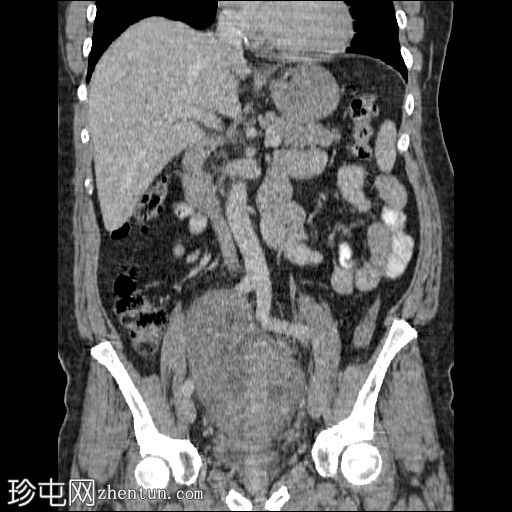

冠状位增强扫描(门静脉期)

盆腔内可见一大小为12 x 17 cm的边界清晰的异质性软组织肿块,向下延伸至下腹部。肿块内未见钙化或脂肪密度影。肿块向下推挤膀胱,并牵拉周围肠袢,但无放射学侵犯证据。未见明显淋巴结肿大、腹水或气腹。未见肺部或骨骼局灶性病变。肝脏可见数个小的单纯性囊肿。患者存在少量Bosniak I型肾囊肿,双侧肾盂肾盏系统饱满。曾行胆囊切除术。